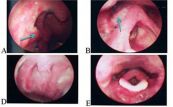

Viêm xoang mạn tính là một bệnh lý thường gặp ở khoang mũi. Viêm xoang gây nhiều khó chịu cho người bệnh nếu không có cách kiểm soát bệnh hiệu quả. Cùng eLib.VN tìm hiểu về bệnh lý này với bài viết dưới đây nhé!

Viêm xoang cấp tính thường do cảm lạnh vì nhiễm virus gây ra. Các triệu chứng phổ biến gồm tắc mũi hoặc nghẹt mũi, dịch vàng hoặc xanh đặc dày...Dưới đây là một số thông tin chi tiết về bệnh viêm xoang cấp tính, mời các bạn tham khảo!

Trong nhiều năm trở lại đây, viêm xoang đã trở thành một trong những vấn đề nhiễm trùng phổ biến. Tình trạng viêm này phát sinh ở các hốc xoang cạnh mũi, nơi sản xuất chất nhầy cần thiết cho đường mũi hoạt động hiệu quả. Trong một số trường hợp, vấn đề trên còn có nguy cơ dẫn đến nhiễm trùng xương hay thậm chí là viêm màng não. Cùng tham khảo bài viết ngay sau đây để biết nguyên nhân và cách điều trị hiệu quả nhé!